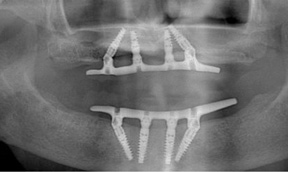

Fig 17. A three-implant fixed bridge may be an immediate-load alternative for a fixed restoration as opposed to a two-implant overdenture. In addition to significant cost reduction due to pre-manufactured components, the final long-term restoration is delivered on the day of surgery.

Figure 17

Fig 18. A three-implant fixed bridge may be an immediate-load alternative for a fixed restoration as opposed to a two-implant overdenture. In addition to significant cost reduction due to pre-manufactured components, the final long-term restoration is delivered on the day of surgery.

Figure 18

As an alternative to the relatively expensive traditional hybrid restoration that the senior population may perceive as unattainable at their age, an immediate-load all-resin provisional may often be a reasonable option as an entry-level prosthesis. This can serve for extended periods or indefinitely, and when made with a sufficient volume of resin and opposing a light occlusion such as a maxillary denture, it can offer the benefit of fixed retention at a significant reduction in expense (Figure 15 and Figure 16). Technology involving a guided approach for placing three implants universally in the same sites with pre-manufactured, one-size-fits-all bar components in the mandible can now allow placement of a final restoration in one day, again at a significantly reduced cost (Figure 17 and Figure 18).24-26 Both of these fixed options—the resin long-term provisional and the three-implant bridge—are economically comparable to the most commonly considered implant prosthesis for elderly patients, the two-implant overdenture. In contrast to the latter, however, both fixed restorations offer significant advantages in bite force, bone preservation, maintenance, and patient satisfaction that are simply unachievable with the removable implant overdenture prosthesis.27-31